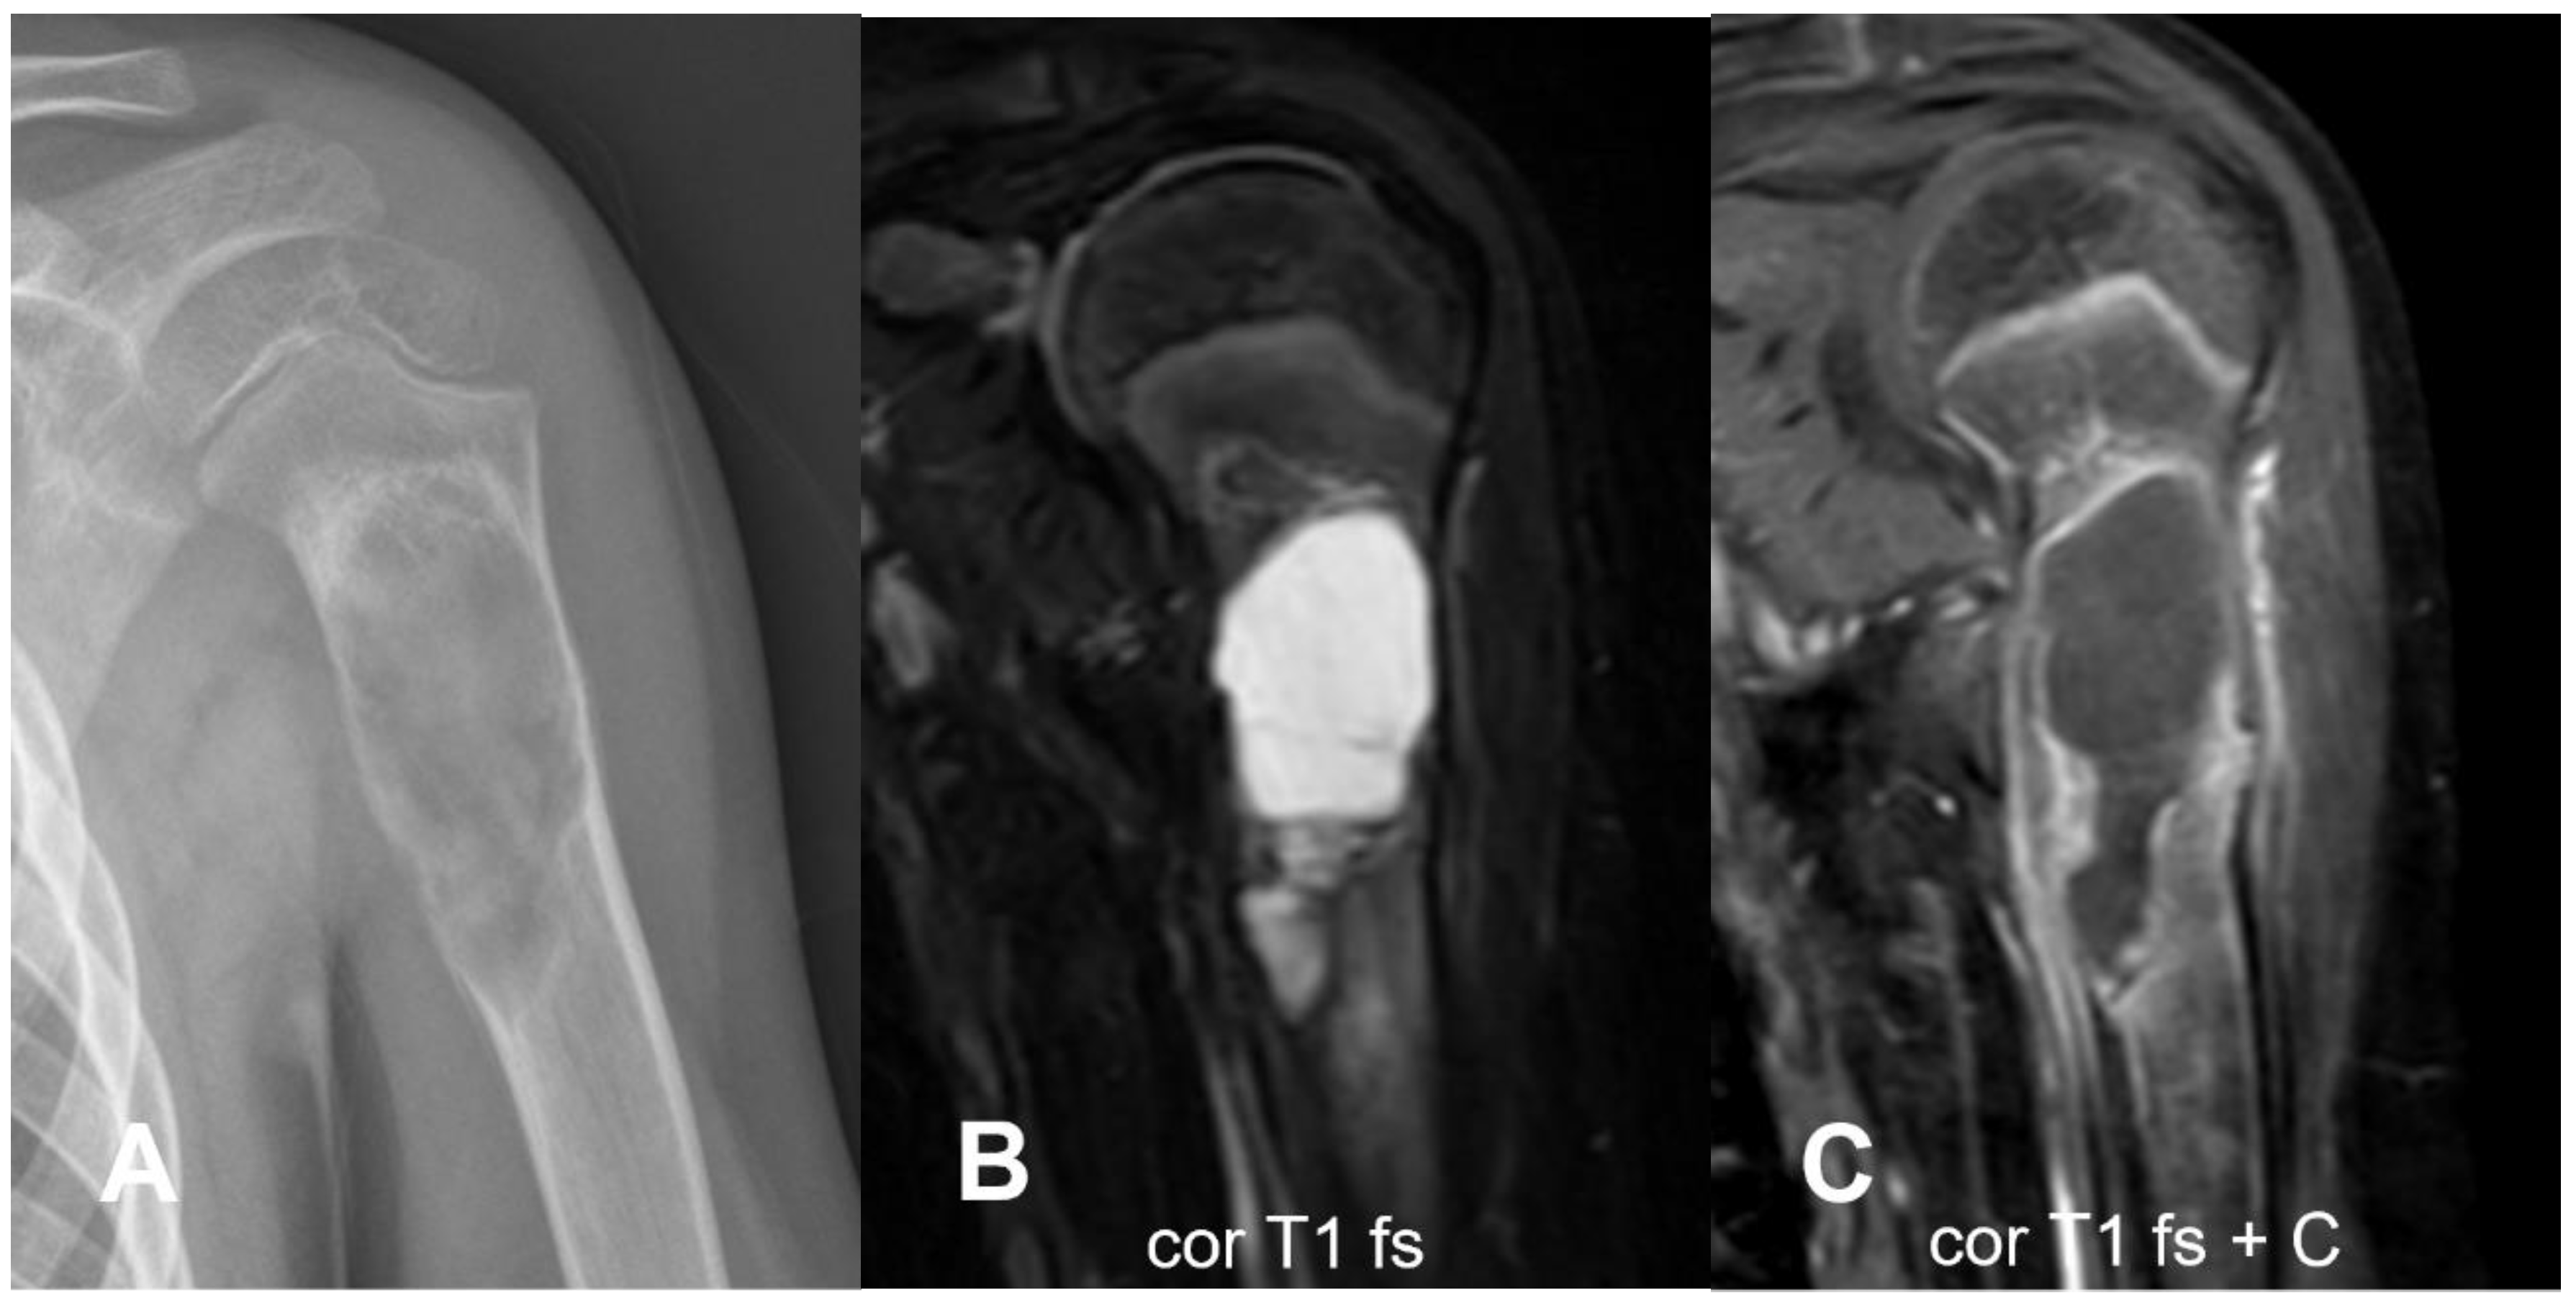

3.1.1. Conventional Osteosarcoma

- Sangle, N.A.; Layfield, L.J. Telangiectatic Osteosarcoma. Arch. Pathol. Lab. Med. 2012, 136, 572–576. [Google Scholar] [CrossRef] [PubMed]

- Angelini, A.; Mavrogenis, A.F.; Trovarelli, G.; Ferrari, S.; Picci, P.; Ruggieri, P. Telangiectatic Osteosarcoma: A Review of 87 Cases. J. Cancer Res. Clin. Oncol. 2016, 142, 2197–2207. [Google Scholar] [CrossRef] [PubMed]